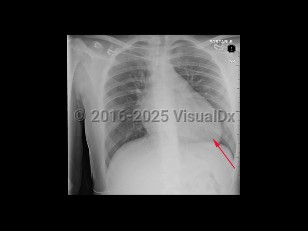

Hypertrophic cardiomyopathy

Hypertrophic cardiomyopathy is caused by an abnormality of heart muscle, usually caused by a genetic mutation of a sarcomeric protein, that results in disrupted myocardial alignment known as myocardial disarray. The result is regional hypertrophy with variable involvement of myocardium. Hypertrophy of the basal septum, adjacent to the left ventricular outflow tract (LVOT), may result in outflow obstruction.

Presenting symptoms are variable, and many patients remain asymptomatic for decades. When symptoms develop, they are often associated with LVOT obstruction and may include dyspnea, palpitations, syncope, or sudden cardiac death. HCM can be diagnosed at any stage of life. It is the most common cause of sudden cardiac death in young athletes.